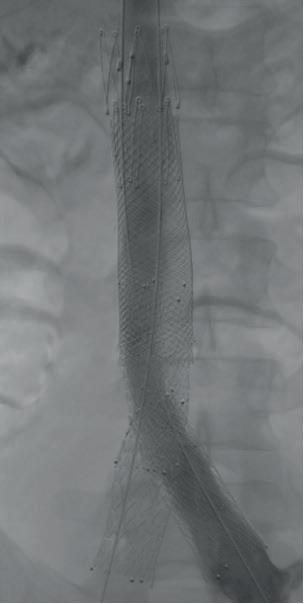

All of which raises the question of treatment modality, and which cases point to which method of re-intervention. In most scenarios, Hemingway outlines, the most effective modality to remove in-stent thrombosis is mechanical thrombectomy with the RevCore thrombectomy catheter (Stryker/ Inari)—except in the setting of couple-ofweeks-old acute stent thrombosis.

associated iliofemoral thrombosis. The IVC and common iliac vein (CIV) stents were thrombosed.

“Both sides had gone down,” Hemingway explains. “One was thrombosed all the way through, the other had a wisp of flow going through it. I took the patient for a venogram and tried aspiration without success, so then tried the RevCore. What we got out was all white, rubberish, fibrotic material. This is someone in whom, had I opted for aspiration thrombectomy, I would have had to reline the whole stent reconstruction. We were able to clean out the stent and send the patient home without any new stents being placed.”

Post-intervention, the patient was noted to have brisk flow on venogram, no thrombus layering on intravascular ultrasound (IVUS), and no further stenting was

Sequential images demonstrate treatment of in-stent thrombosis using the RevCore catheter, showing complete thrombus removal and restoration of luminal patency 1 2 3

RevCore mechanical thrombectomy in action

Hemingway recalls a classic case using the RevCore Thrombectomy Catheter that underlines why the modality is his go-to in these types of scenarios.

The patient was a 35-year-old male who presented with worsening back pain, leg swelling and edema that on imaging appeared to point to an acute DVT. Several years prior, he had undergone thrombectomy, IVC stenting and a bilateral iliocaval reconstruction for chronic IVC occlusion and

required. Now 18-months post-procedure, the patient has sustained full patency and complete symptom resolution.

Decisions around intervention are influenced by timing, Hemingway points out. “If a patient has an occluded stent for six months or longer, I think that the results are less predictable and it is a little harder to know whether you’re going to get great thrombus clearance,” he says. “If it is a case of less than six months and definitely less than three months, my experience has been that RevCore has worked very well for clearing out in-stent thrombosis. If you are patient, and really work the areas, you use the device correctly and really grind away at that thrombus layer by layer, you will get it cleared out. Once it gets to be rock hard or associated with calcification, there’s just some pathology you can’t pull out of there.”